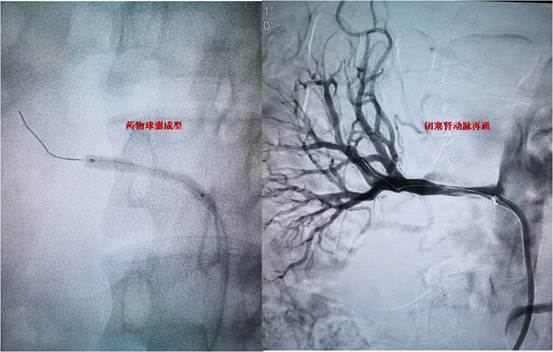

图-3 闭塞肾动脉再通

患者,未成年男性,在当地因高血压病就诊检查,发现可能存在肾动脉狭窄可能,患者血压最高达200/146mmHg,为进一步诊治慕名来到交大一附院血管外科杨林教授门诊。患者入院后,在科室禄韶英主任指导下,杨林教授及诊疗团队韩阳医师,武士琪医师,李小兵医师对其进行了完善的术前检查、术前准备及药物治疗。进一步明确患者为肾动脉闭塞,手术难度极大,手术风险极高。考虑到患者未成年,为保留患者潜在的肾功能,同时避免采用常规的金属支架技术。杨林教授团队经过详细的术前讨论后和设计手术方案后,决定给患者实施局麻微创的药物球囊成型技术。在介入手术室的配合下,发现患者为右肾动脉闭塞,远端通过毛细血管代偿,手术团队通过精细的微创技术,反复尝试都未能通过闭塞段血管,最后通过各种微导丝、微导管技术的联合应用终于通过闭塞的肾动脉,然后通过小球囊预扩张,过渡到常规球囊扩张,最后为患者实施药物球囊扩张成形术,患者闭塞的肾动脉得到完美重建。患者术后在血管外科医护团队的严密监控下顺利恢复。术后血压即恢复正常,于近日顺利出院。

肾动脉狭窄/闭塞是引起继发性高血压最常见的原因,严重情况下可导致肾动脉闭塞,肾功能衰竭、肾萎缩,甚至需要肾切除。传统开放手术和介入手术治疗风险大、并发症高,因此,肾动脉闭塞患者往往得不到有效救治,而最终发展为肾衰竭状态,此类患者属于疑难复杂病症,在国际、国内开展均较少。此次肾动脉闭塞的微创手术患者的成功救治,标志着我院血管外科在处理复杂肾动脉疾病救治能力的提升。近年来,血管外科杨林教授近年来致力于腹主动脉瘤、下肢动脉硬化闭塞的临床诊疗工作,开展、完成西北首例、省内首例血管手术十余例,填补多项地区空白。血管外科团队将以饱满的热情服务于广大血管病患者。